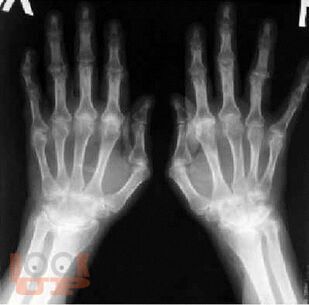

Современные возможности диагностики ревматических заболеваний

В учебном пособии изложены современные представления о методах диагностики ревматических заболеваний. Учебное пособие оснащено тестовыми заданиями и ситуационными задачами различной степени сложности для самоконтроля знаний с эталонами ответов. Учебное пособие предназначено для самостоятельной аудиторной и внеаудиторной работы студентов, обучающихся по специальности «Лечебное дело».